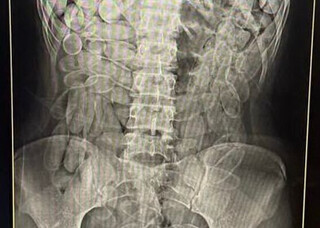

Na semana passada, duas jovens bolivianas de 20 e 17 anos foram presas em uma fiscalização no Posto Esdras, em Corumbá, após terem confessados ter ingerido, cada uma, 102 cápsulas de cocaína. Casos como esse são frequentes, e registrados quase que diariamente na fronteira de Corumbá. As duas tentavam passar pela fronteira em um táxi clandestino.

Após confessarem estar com a droga no estomago, as jovens foram encaminhadas para a Santa Casa do município, onde exames confirmaram a presença de 2,2 quilos de drogas.